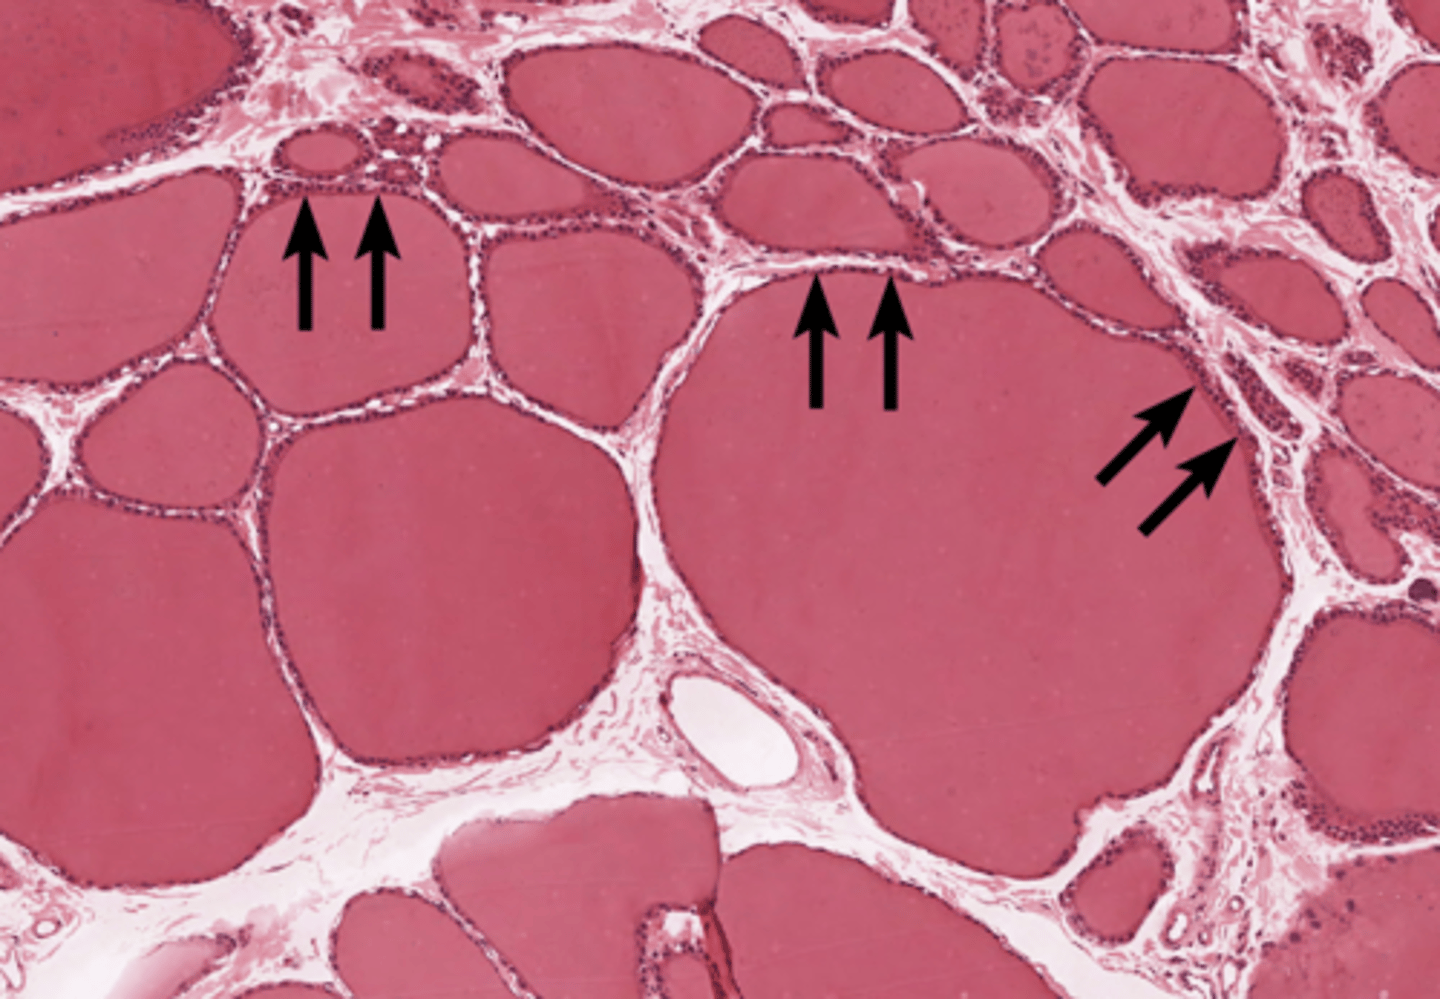

Parathyroid gland

Oxyphil cell

Principal cell